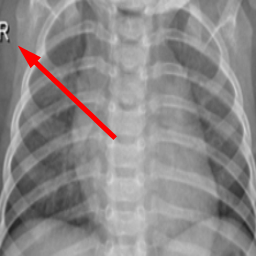

Many images in the dataset contain annotations or marks made during the image acquisition or afterwards by a radiologist. Examples of such images are presented in Fig. 3. Such symbols in the training dataset are known to generate biases as classifiers tend to target their attention to the presence of the symbols instead of genuine features of the image Rajaraman and Antani (2020); DeGrave et al. (2021). Therefore after the initial preprocessing, consisting of cropping and resizing all images containing such elements were removed.